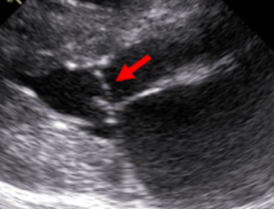

SAM은 HCM의 약 30~50%에서 관찰되는 현상이다.

AMV에 의해 좌심방 유출로가 막히는 현상을 지칭한다고 이해하면 된다.